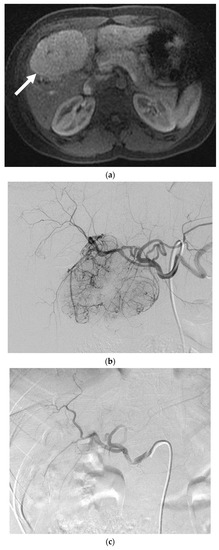

One patient with two lesions was treated with PVA particles for the treatment of abdominal pain (Figure 2). Both lesion volumes decreased by more than 50%. As per RECIST, one lesion was stable and one had a partial response. The patient had resolution of her abdominal pain at her one-month follow-up. There were no complications.

Figure 2.

A 24-year-old female with focal nodular hyperplasia (FNH) and right upper quadrant pain. (a) Magnetic resonance imaging (MRI) with contrast demonstrates a hypervascular lesion in segments 4 and 5 (solid white arrow). Twenty-minute delayed images showed continued enhancement (not shown). (b) Angiogram reveals segment 4 and segment 5 arteries that feed a hypervascular mass. Each artery was infused with 200 and 300 µm PVA particles until stasis. (c) Post-embolization angiogram shows no flow to the FNH. (d) MRI with contrast one month after embolization reveals no residual enhancement and a decrease in the size of the FNH (solid white arrow). The patient’s pain resolved following the embolization.